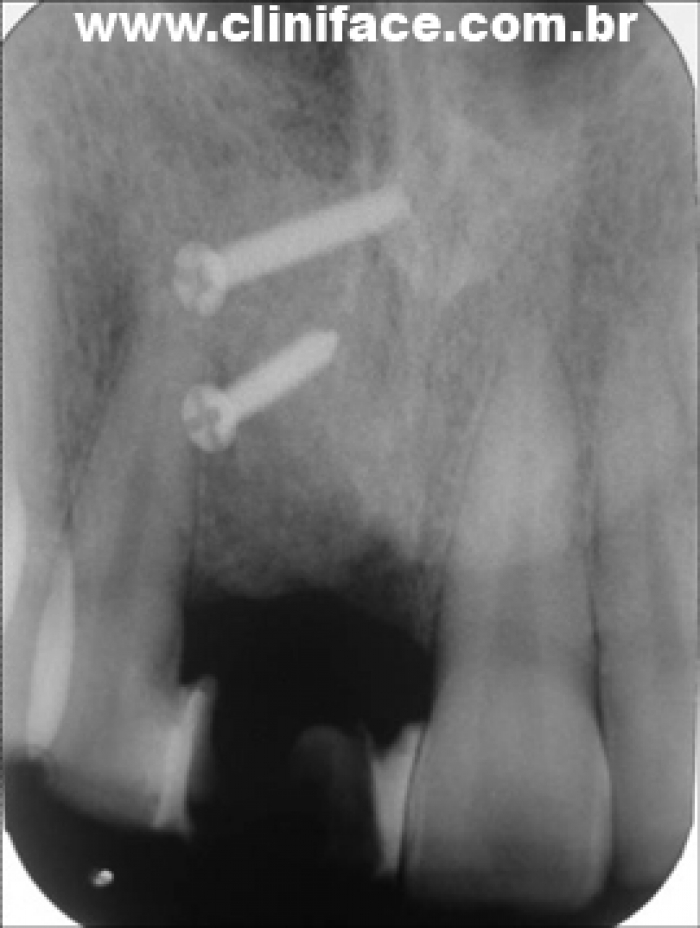

Raio X após o enxerto ósseo

Raio X de controle realizado dia 01/04/2013